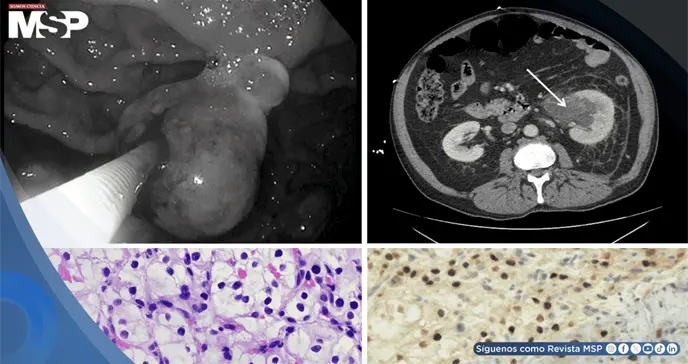

Para encontrar la causa, los médicos le realizaron una tomografía computarizada (TAC) de su abdomen y pelvis. Las imágenes revelaron una masa grande en la parte inferior de su riñón izquierdo, que tenía todas las características de un carcinoma de células renales, el tipo más común de cáncer de riñón.

Pero la TAC mostró algo más: signos de que el cáncer podría haberse diseminado, incluyendo ganglios linfáticos agrandados en el abdomen, nódulos en los pulmones, lesiones en el hígado y, de manera intrigante, una masa dentro de la cavidad de su estómago.

Ante este último hallazgo, los gastroenterólogos le hicieron una endoscopia. Este procedimiento confirmó la presencia de una masa ulcerada y abultada en el cuerpo del estómago, de la cual tomaron muestras (biopsias) para analizarlas al microscopio.

Al correlacionar la biopsia con las imágenes de la TAC, quedó claro que la masa grande en el riñón izquierdo era el tumor primario, y que las lesiones en el estómago, pulmones, hígado y ganglios eran metástasis.